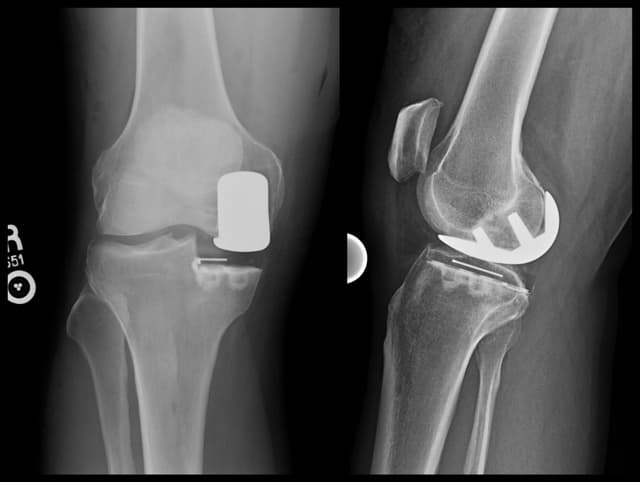

Post-op